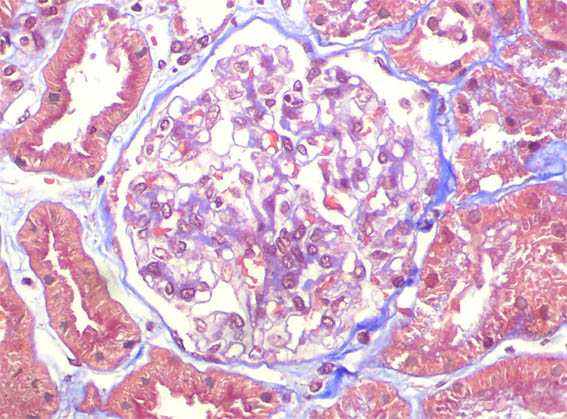

Figure 3. Masson's trichrome stain, X400.